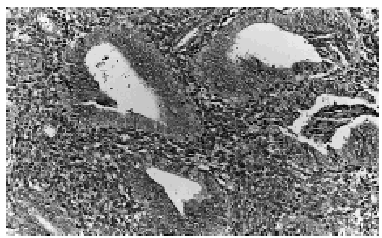

El estudio histológico del nódulo demostró la presencia de glándulas endometriales con un estroma densamente celular, localizadas en el espesor del tejido colágeno dérmico, sin alcanzar la epidermis ni el tejido adiposo subyacente (fig. 1). Dichas glándulas mostraban luces irregulares, pseudoestratificación de los núcleos y figuras de mitosis, características típicas de un endometrio de tipo proliferativo (fig. 2). El estudio inmunohistoquímico reveló positividad para receptores de estrógenos (6F11) (fig. 3) y progesterona (1A6).

Fig. 1.--Glándulas de aspecto endometrial, rodeadas de estroma en el seno del tejido conjuntivo dérmico.